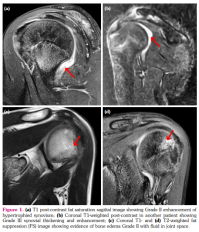

a) Synovial hypertrophy score: Thirteen (40.6%) joints in nine patients revealed synovial hypertrophy with a mean grade score of 0.7±0.9 (Figure 1 a, b). Five joints had Grade I and eight joints had Grade II synovial hypertrophy (Figure 2a). The number of joints with synovial hypertrophy in sJIA, ERA, and undifferentiated JIA were seven (53.8%), four (30.7%), and two (15.3%) joints, respectively.

b) BME score: Twenty-one (65.6%) joints in 13 patients revealed BME with a mean grade score of 1.1±1.0 (Figure 1c, d). The number of joints which had Grade I, II and III BME scores were 11, seven, and three, respectively (Figure 2a). The number of joints with BME in sJIA, ERA, and undifferentiated JIA was 13 (61.9%), five (23.8%), and three (14.2%) joints, respectively. Of these 21 joints, only two joints revealed BME with no other findings and the rest 19 joints showed synovial effusion or one or the other MRI parameter of joint inflammation. There was no statistically significant difference in the occurrence of BME in sJIA subset versus the rest of the JIA subsets (p=0.823).

In addition, the presence or absence of synovial effusion on MRI was also noted. Joint effusion was seen as hyperintensity adjacent to synovium on post-contrast T1-weighted images.